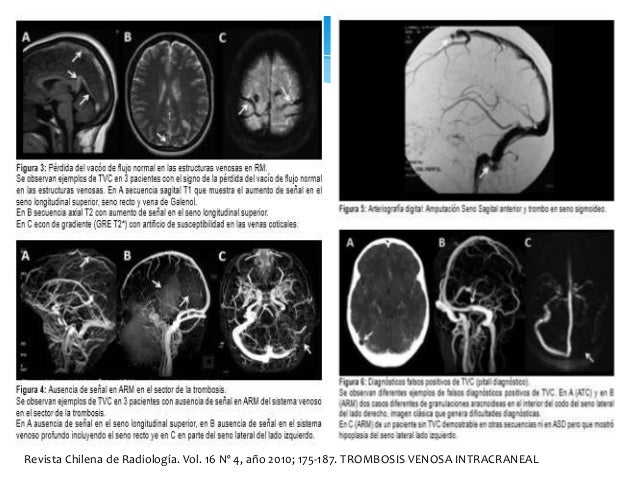

19. 19. SIGNO DEL DELTA (a) Recanalización del trombo dentro del seno, (b) Organización del coágulo, (c) Alteración de la barrera hematoencefálica , (d) Dilatación de colaterales venosas durales y peridurales. Signos del seno hiperdenso y de la cuerda: En imágenes por RM sin contraste, los vasos son habitualmente hipointensos en todas las secuencias debido a su flujo; ésto se denomina vacío de señal por flujo o también llamado “vacío de flujo”. Revista Chilena de Radiología. Vol. 16 Nº 4, año 2010; 175-187. TROMBOSIS VENOSA INTRACRANEAL

20. 20. Revista Chilena de Radiología. Vol. 16 Nº 4, año 2010; 175-187. TROMBOSIS VENOSA INTRACRANEAL

21. 21. Revista Chilena de Radiología. Vol. 16 Nº 4, año 2010; 175-187. TROMBOSIS VENOSA INTRACRANEAL